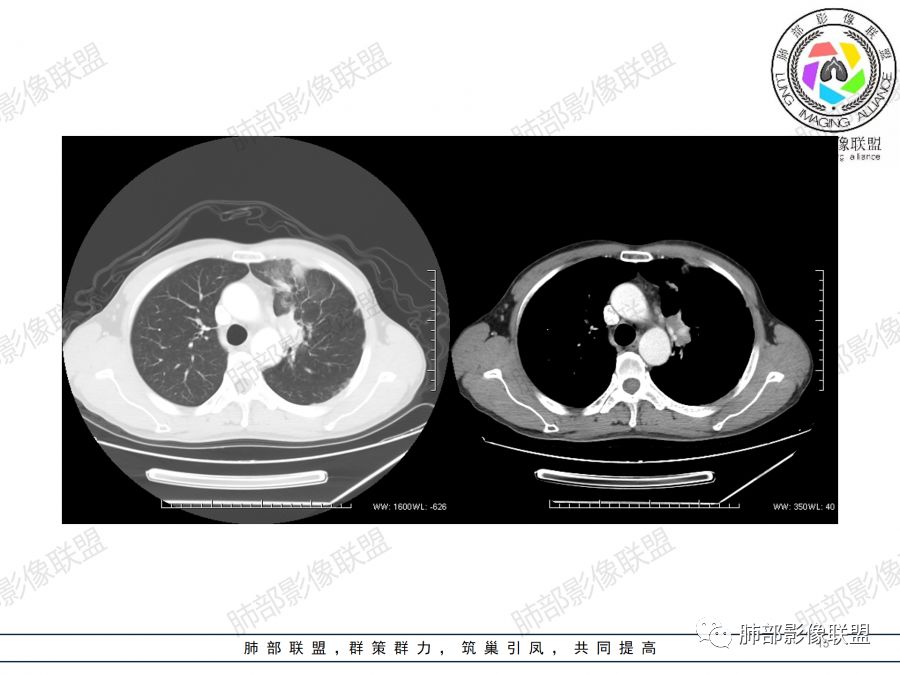

1.中年男性,慢性病程,以咳嗽咳痰为主;

2.双上肺多发病灶,左肺上叶病灶沿血管支气管束分布,由外朝内,以平直收缩为主,周围有斑片渗出,胸膜糊墙,支持炎性病灶或是伴有肿瘤灶可能性。

两上肺发病,多支持结核等感染,但结核基础上伴发肺癌并不鲜见!

3.病灶内多支支气管粘液栓,炎性及恶性均可,但是炎性多于恶性;强化杂乱不均,病灶内小灶坏死比规则,支持炎性肉芽肿病变。

鳞癌病灶如较大,强化常不够显著且多见相对大范围湖泊样坏死。

4. 应仔细观察病变的支气管情况,如果支气管出现腔内结节或阻塞征象,需要提示临床干预,用支气管镜、穿刺等手段来进一步确诊。

5.  本例的焦点主要集中在结核与周围型肺鳞癌的鉴别诊断上!

病灶与大气道的关系未能满意呈现,但如此大范围病灶紧贴胸膜却未见胸壁纵隔组织结构侵犯破坏是不大符合肺鳞癌的生物学行为的。